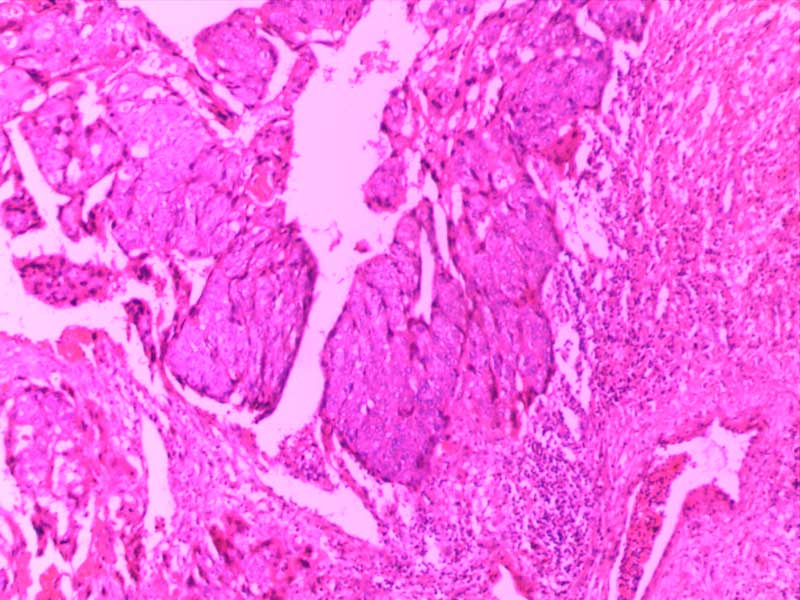

绒毛膜癌-10倍

肉芽组织-10倍

乳头状瘤(膀胱)4倍

乳腺癌-4倍

乳腺癌-10倍